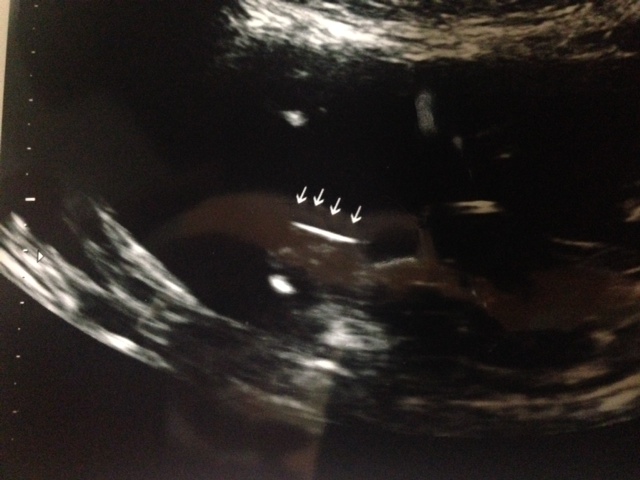

We were very excited, but a bit confused. We both thought we were actually looking at a picture of a boy. I've been studying the three-white lines of confirmed girl ultrasounds, but this looks a bit different. The line in the middle (with the arrow) seems to be, eh, protruding! It also looks like it might be two lines? Or am I looking at the wrong thing? Are the two thick white lines on the side her legs or her labia? Or neither because she's actually a he!

PS - Here's a second pic the tech said connoted gender. She said that flat line said girl - but she didn't say what it actually was.

I can't figure out what the second pic is but the first one looks very girly to me x

Girl for sure! First image is showing labial folds. 2nd image is a side view of clitoris. Congrats